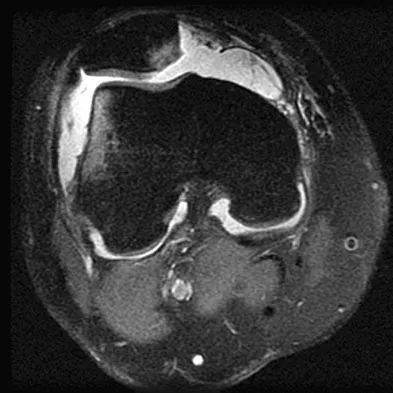

Figure 49 shows an acute axial MRI scan of a left knee. What is the most likely diagnosis?